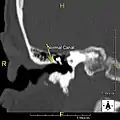

Normal ear canal

The normal ear canal is approximately 7 mm in diameter and has a volume of approximately 0.8 ml (approximately one-sixth of a teaspoon).[4] As the condition progresses, the diameter narrows and can even close completely if untreated, although people generally seek help once the passage has constricted to 0.5–2 mm due to the noticeable hearing impairment. While not necessarily harmful in and of itself, constriction of the ear canal from these growths can trap debris, leading to painful and difficult to treat infections.